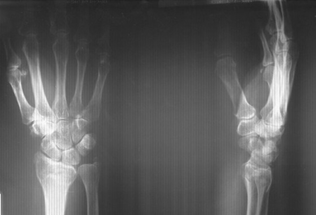

В группе 3 на рентгенограммах через 3, 6 и 12 месяцев у 11 (64,7%) пациентов наблюдалось снижение суставной щели в лучезапястном, среднезапястном и запястно-пястном суставах [в среднем 1,0-1,5 мм (± 0,2)] и неравномерность ладьевидно-полулунного и полулунно-трехгранного промежутков (рис. 3). Нарушение целостности запястных арок наблюдалось в 12 (70,5%) наблюдениях. На МРТ у 6 (35,3%) пациентов были выявлены признаки асептического некроза.

Рис. 3. Рентгенограмма кистевого сустава пациента из группы 3 через 6 месяцев после открытого вправления вывиха с применением АВФ. Определяются признаки субхондрального склероза полулунной кости

У пациентов группы 4 на рентгенограммах через 3, 6 и 12 месяцев суставная щель в лучезапястном, среднезапястном и запястно-пястном суставах была в пределах нормы [в среднем 2-2,5 мм (± 0,1)], ладьевидно-полулунный и полулунно-трехгранный промежутки – равномерные, и наблюдалась целостность запястных арок. В боковой проекции соотношение ладьевидной, полулунной, головчатой и трехгранной костей правильное, соосность суставных поверхностей не нарушена (рис. 4). На МРТ не были выявлены признаки асептического некроза полулунной кости и карпальной нестабильности.

Рис. 4. Рентгенограмма кистевого сустава пациента из группы 4 через 6 месяцев после открытого вправления вывиха с фиксацией спицами и шва связок кистевого сустава